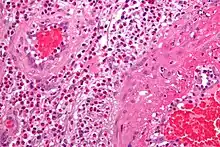

- The definite diagnosis of vasculitis is established after a biopsy of involved organ or tissue, such as skin, sinuses, lung, nerve, brain, and kidney. The biopsy elucidates the pattern of blood vessel inflammation.

- Some types of vasculitis display leukocytoclasis, which is vascular damage caused by nuclear debris from infiltrating neutrophils.[14] It typically presents as palpable purpura.[14] Conditions with leucocytoclasis mainly include hypersensitivity vasculitis (also called leukocytoclastic vasculitis) and cutaneous small-vessel vasculitis (also called cutaneous leukocytoclastic angiitis).